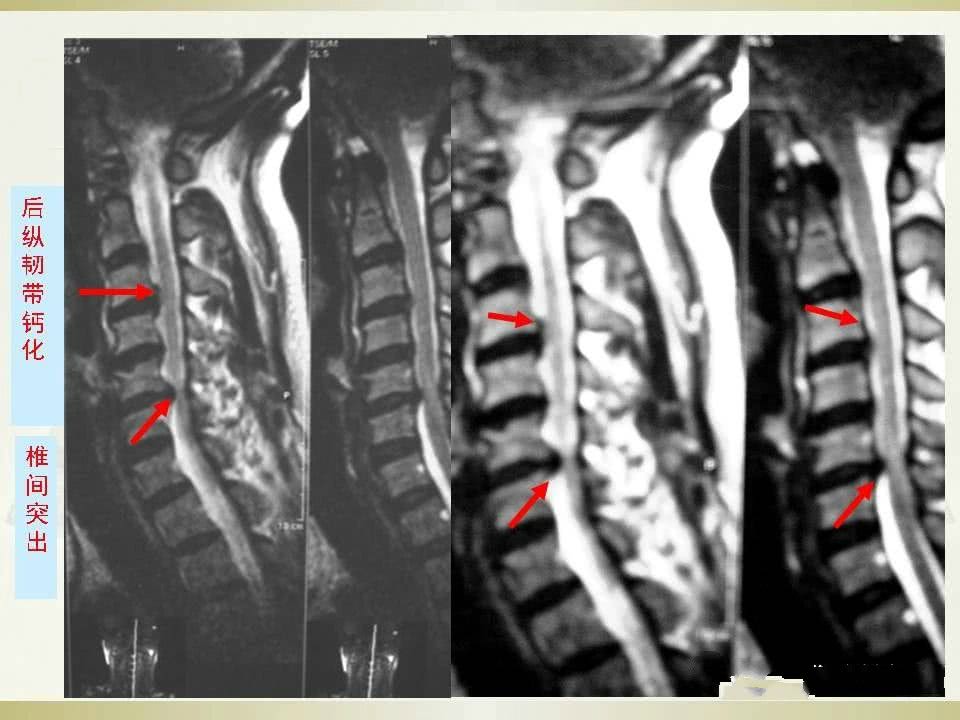

颈椎病的影像学诊断及临床分型汇总

颈椎病的诊断 1、临床表现与影象学所见相符合者,可以确诊。2、具有典型颈椎病临床表现,而影象学所见正常